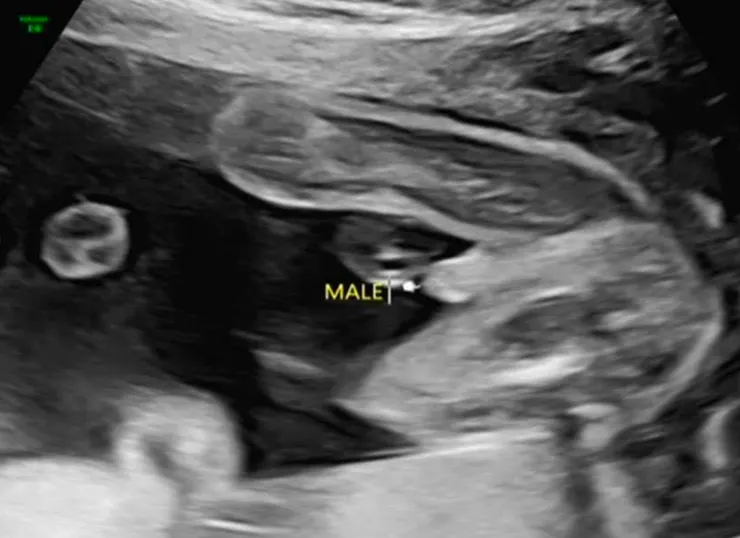

終於來到高層次超音波這關!高層次這關最緊張的應該是我老公,因為前兩次照一般超音波時,醫生就覺得應該是男寶寶無誤,但我老公拒絕承認男寶寶!他說一定要等到高層次他才要確認是男是女。

當然老公最在意的性別⋯⋯

老公:醫生說是男生之後的事我都沒在聽